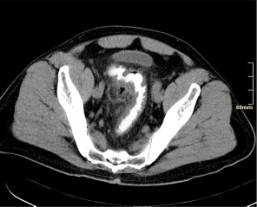

CT mit Kontrastmitteleinlauf :

die Untersuchung der ersten Wahl! Diese Untersuchung liefert rasch Informationen über den Zustand des Kolons und das Ausmaß der Erkrankung. Sie ist für die Akutdiagnostik geeignet (Bild 3).